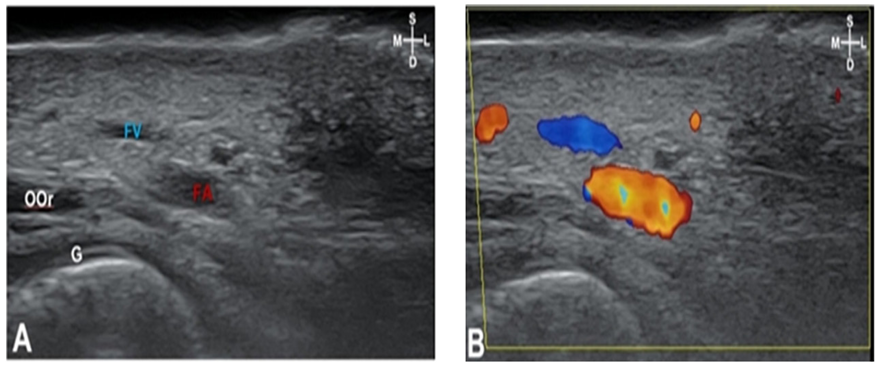

In F1, the facial artery was observed located along the medial margin of the masseter muscle <Fig. 5>. The peripheral structures observed in F2, F3, and F4 were facial muscles, while depressor anguli oris muscles was observed in F2, and orbicularis oris muscles were observed in F3 and F4, respectived <Fig. 6>.

Depressor anguli oris muscles were observed in F2, and the depth from skin to depressor anguli oris muscles was 8.6±2.1 mm, and this muscle was observed in 90% of 40 cases. Orbicularis oris muscles were observed in F3 and F4 <Fig. 5,6>. The depth from skin to orbicularis oris muscles was 9.5±3.3 mm in F3 and 6.3±3.1 mm in F4, respectively <Table 2>.

Fig. 5. Sonography (A) and doppler image (B) of F3: The arteries were located posterior to the orbicularis oris (OOr). The depth of the facial artery is 6.9 mm. Depth of skin to the OOr is 9.5mm. The dotted line, OOr located in arch shape; Blue, facial artery; S: superficial; D: deep; M: medial; L: lateral